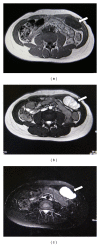

A 29-year-old female had presented to surgical outpatient's department complaining of lump in the anterior abdominal wall. Ultrasound and magnetic resonance imaging revealed a solid degenerated tumor in the anterior abdominal wall. It was surgically excised, and histopathology confirmed it to be "ancient" schwannoma. To our knowledge, this is the second reported case of an abdominal wall ancient schwannoma in the medical literature.